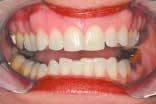

The assistant retracts the lips for the next set of images. These two images are the arches in occlusion and slightly open. The image of the teeth in occlusion gives us information on overbite, overjet, cross bites, gingival recession, Golden Proportion, Shimbashi number, and exostosis. A periodontal probe can be placed on the central incisor as a reference for measurement. This view can be used to analyze and diagnose Golden Proportion on a printed view with a ruler and pen or with measurement tools found in many software applications.

The next image of the arches slightly open allows the patient to see the lower anterior teeth, which are often covered by the maxillary teeth. This also allows us to evaluate the arch form and the curve of Spee and Wilson. A neuromuscular arch incoordination will begin to show as one side of the mandibular arch may drop more than the other side. This shot can be captured with a shade tab in the same plane with the maxillary incisors to demonstrate the shade to patient.